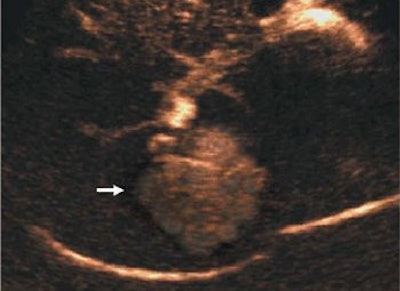

| Transverse contrast-enhanced US scans obtained in contrast-specific mode with pure harmonic detection in 45-year-old woman show typical spoke wheel-shaped contrast-enhancement pattern of focal nodular hyperplasia after microbubble contrast agent injection. Above, central spoke wheel-shaped contrast enhancement (arrow) is evident 15 seconds after the injection (arterial phase). Middle, contrast enhancement (arrow) is diffuse and homogeneous 25 seconds after the injection (arterial phase). Below, contrast enhancement is hyperechoic 105 seconds after the injection, with a central hypoechoic region that corresponds to the central scar (arrow) that is evident during the late phase. |

| Quaia E, Calliada F, Bertolotto M, et al, "Characterization of Focal Liver Lesions with Contrast-specific US Modes and a Sulfur Hexafluoride-filled Microbubble Contrast Agent: Diagnostic Performance and Confidence," Radiology 2004;232:420-430, figure 8a-c. |